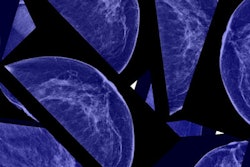

Mammography and orthopedic imaging firm Planmed has received 510(k) clearance from the U.S. Food and Drug Administration (FDA) for its 2D full-field digital mammography device.

Clarity 2D offers an array of features including customizable image processing and a digital detector that enables it to function in extreme conditions, the company said. The device received the European Economic Area's CE Mark in 2016.